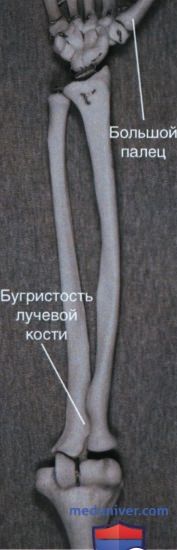

Радиоульнарный угол: строение и особенности лучевой кости